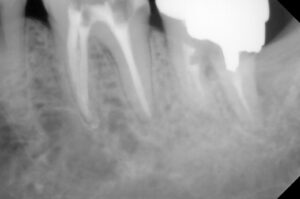

そこで、局所麻酔下で神経の頭の部分を除去し

1時間半ほどかけて神経組織固定と薬液を塗布

自費診療:19500円

同年1/15 薬液除去し最終パッキング材で蓋をし

土台を作成する型取りをして仮詰めで終了

1時間半の工程で自費: 19500円+リーマ代2800円

同年1/29 できてきたファイバーコアの土台をset

保険診療であれば仮歯調整して今回は終了し

次回形成と印象になりますが

患者さんに時短の説明をし納得いただけたので

続けて形成した後に印象を取り仮歯の調整まで

2時間超で自費診療:26000円+技巧代7600円

同年2/19 最短で根の処置から被せるまでこぎ着け

E-max set 自費:75000円

レントゲンでは神経の詰め物の状態の違い→